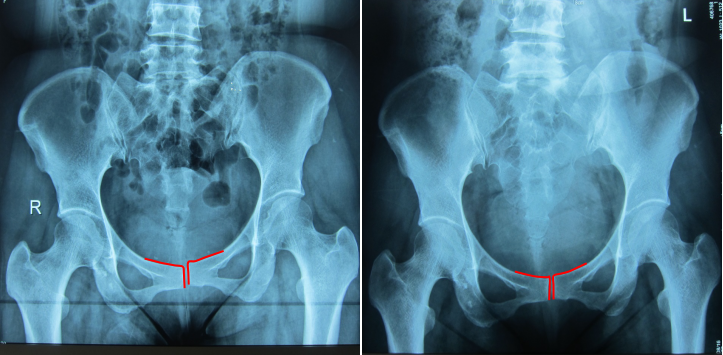

治疗前后骨盆关节错位对比

治疗前 治疗后